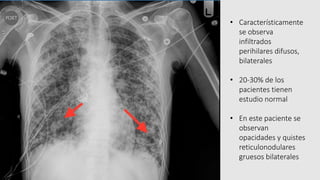

• Característicamente

se observa

infiltrados

perihilares difusos,

bilaterales

• 20-30% de los

pacientes tienen

estudio normal

• En este paciente se

observan

opacidades y quistes

reticulonodulares

gruesos bilaterales